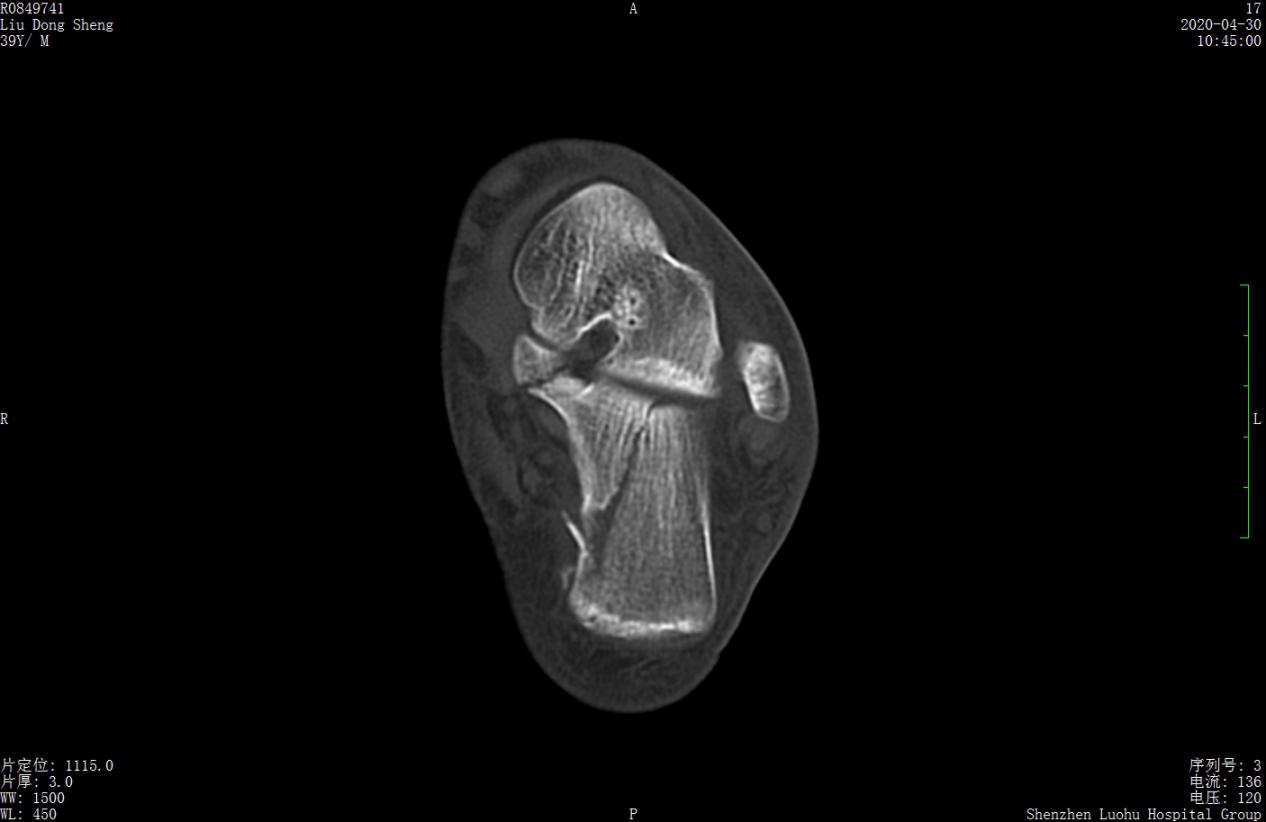

案例2影像

术前X线示骨折分离移位